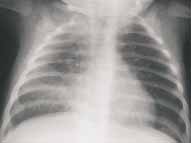

Cuando estas infecciones ocurren usualmente el proceso viral precede al cuadro bacteriano. Clínicamente estos pacientes presentan signos y síntomas de un proceso viral y abruptamente se tornan demasiado enfermos y tóxicos, esta es una clave clínica y alerta sobre la necesidad de revalorar el cuadro con una nueva radiografía, la cual usualmente puede ser confusa, presentándose el patrón intersticial de base típico de los procesos virales acompañado de un espectro variable de los hallazgos descritos en los procesos bacterianos (Figura10).4

FIGURA 10. Paciente lactante menor con cuadro de infección viral inicial con posterior sobreinfección por neumococo.

Observe el aumento del volumen pulmonar y los infiltrados intersticiales característicos de los procesos virales,

con infiltrados alveolares difusos en la base pulmonar derecha por sobreinfección bacteriana.